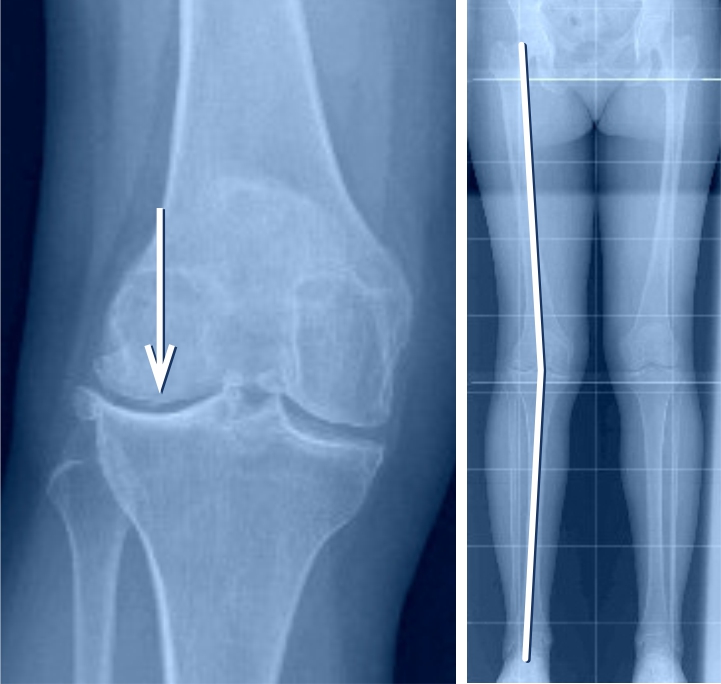

Im Verlauf des Lebens kommt es zu natürlichen Veränderungen der Beinachse. Säuglinge werden mit O-Beinen geboren. Nach dem Kleinkindalter verändert sich die Beinachse zu einem leichten X-Bein. Mit der Pubertät stellt sich dann meist eine gerade Beinachse ein. Dies ist der Fall, wenn sich im geraden Stand bei geschlossenen Beinen Knöchel und Knie an der Innenseite berühren. Bleibt bei sich berührenden Knöcheln zwischen den Knien ein Abstand, spricht man von O-Beinen. Bleibt hingegen eine Lücke zwischen den Knöcheln, während die Knie sich berühren, spricht man von X-Beinen. Beim O-Bein verläuft die gewichttragende Achse durch die innen gelegene Fläche des Kniegelenks, beim X-Bein durch die aussen gelegene.

Für die Kniegelenkarthrose typisch sind belastungsabhängige Knieschmerzen im geschädigten Gelenkbereich, insbesondere bei den ersten Schritten (sogenannter Anlaufschmerz). Eine längere Belastung kann die Beschwerden noch verstärken. Die Varusgonarthrose (O-Bein) schmerzt tendenziell auf der Innenseite des Knies und die Valgusgonarthrose (X-Bein) auf der Aussenseite. Konventionelle Röntgenbilder bestätigen die entsprechende Diagnose.

Wenn nur auf der Innen- oder der Aussenseite des Kniegelenks eine Arthrose vorliegt, kann mit einer sogenannten Umstellungsosteotomie oft eine Linderung der Beschwerden über Jahre erzielt werden, ohne dass ein künstliches Gelenk eingebaut werden muss. Wenn nur die Innenseite des Kniegelenks von der Arthrose betroffen ist (O-Beine), während die äussere Gelenkhälfte völlig schmerzfrei ist, kann mittels Umstellungsosteotomie durch eine Knochendurchtrennung im oberen Schienbeinbereich ein leichtes X-Bein erzielt werden (sogenannte Valgisationsosteotomie), was zur Entlastung der inneren Gelenkhälfte führt. Ziel ist es, unter Erhalt des eigenen Gelenks die Schmerzen zu vermindern und das Fortschreiten der Arthrose aufzuhalten oder zumindest zu verzögern. Zur Behandlung der Valgusgonarthrose (X-Fehlstellung) erfolgen Knochendurchtrennung und Achsenkorrektur knienah meistens am Oberschenkel (Varisationsosteotomie). Ist die Fehlstellung sehr ausgeprägt ist es manchmal sogar notwendig, in derselben Operation am Ober- und Unterschenkel einen Korrektureingriff vorzunehmen.